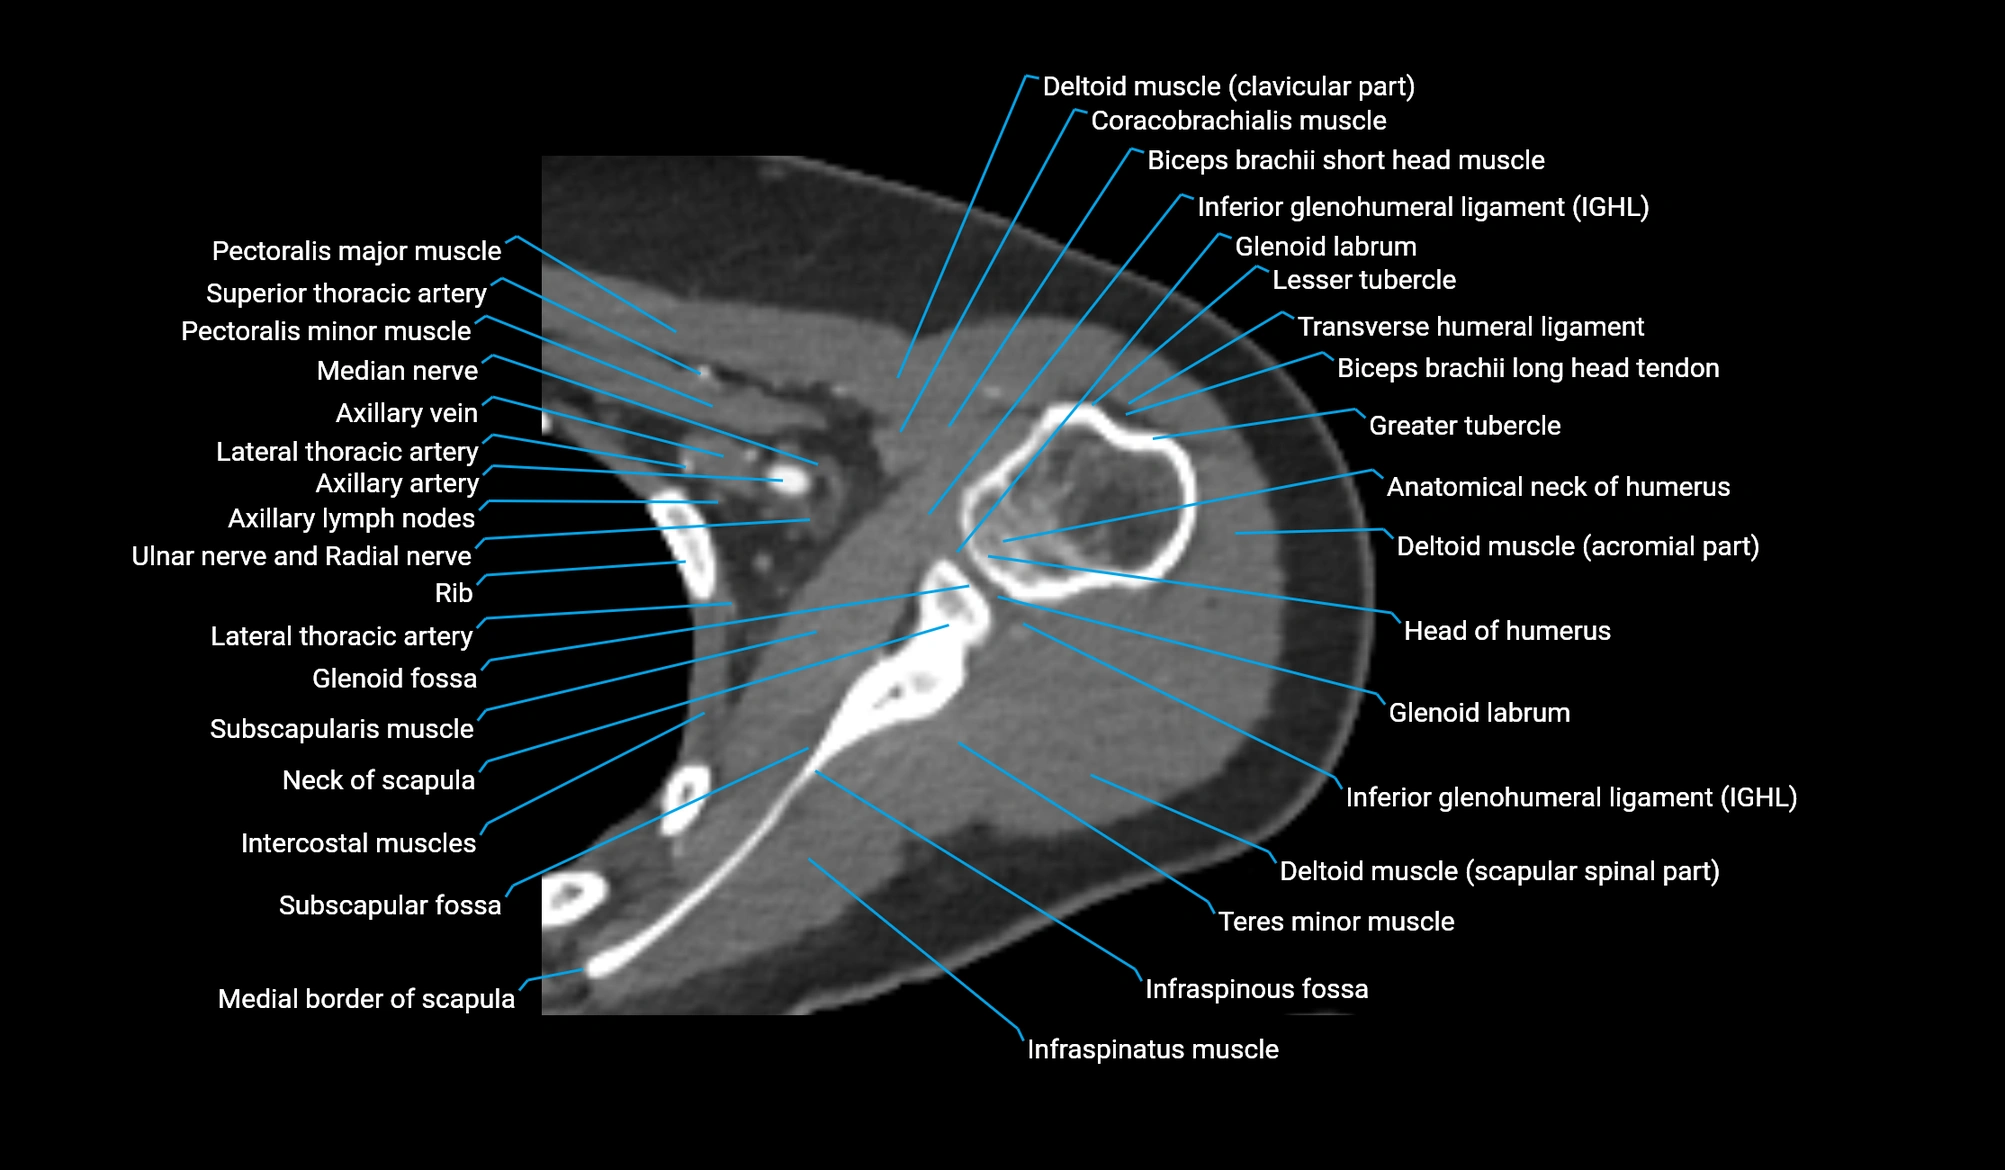

CT image